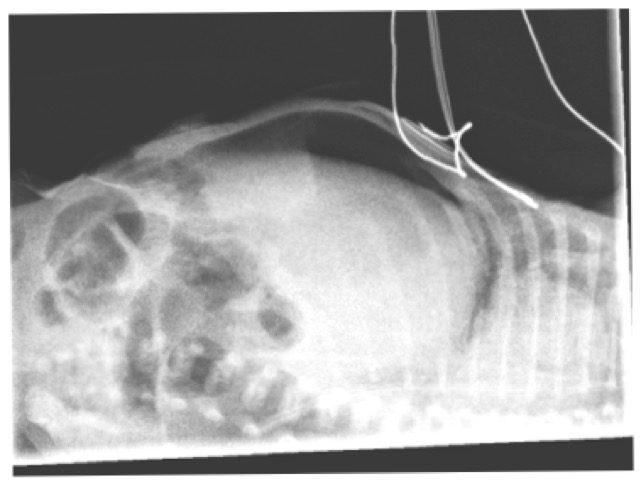

ATRESIE GRELE NN AVEC PNEUMOPERITOINE ET EIP (emphysème interstitiel pulmonaire)